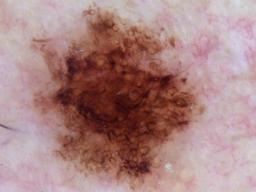

{

"age_approx": 60,

"anatom_site_general": "upper extremity",

"concomitant_biopsy": false,

"diagnosis_1": "Benign",

"diagnosis_2": "Benign melanocytic proliferations",

"diagnosis_3": "Nevus",

"diagnosis_confirm_type": "serial imaging showing no change",

"image_type": "dermoscopic",

"lesion_id": "IL_6731115",

"melanocytic": true,

"sex": "male"